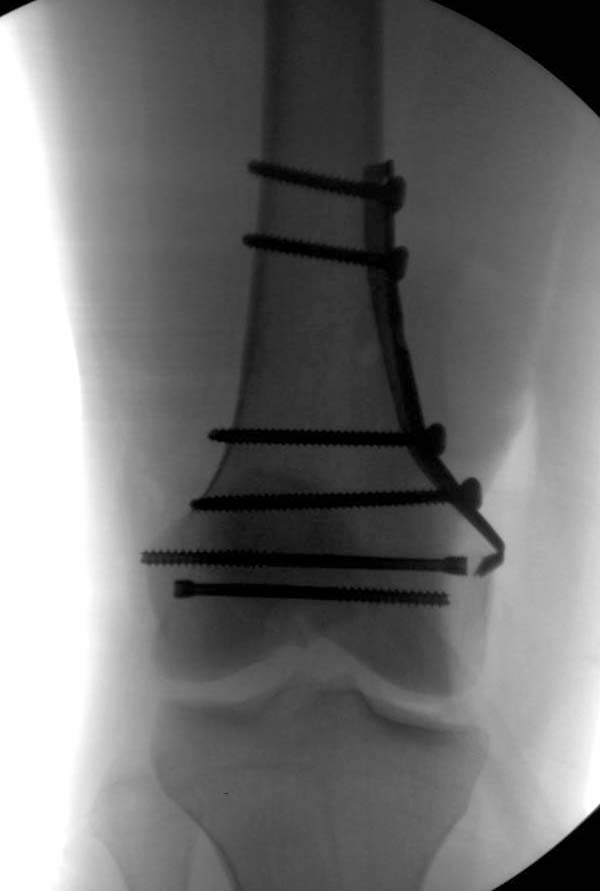

Остеосинтез LCP пластиной

В данном случае предпочтителен парапателлярный доступ, где необходимо создать лучший обзор к мыщелку. После остеотомии и репозиции фиксацию надо проделать поперечными винтами и дополнительно задней antiglade plate - сделанной из 1/3 tubular plate.

Здесь представлены различные варианты фиксации перелома, а также снимки комбинации перелома с повреждением хряща (12-19). Пластика хряща OsseoFit и установка custom made plate.